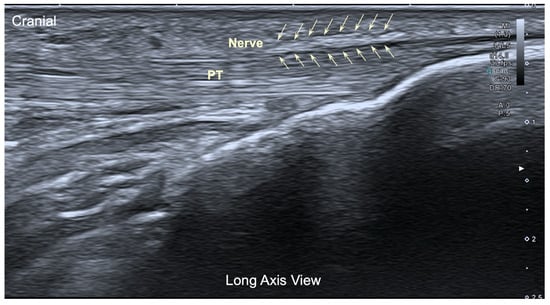

2.4. The Needling Approach on the Fresh Cadaver

2.5. The Percutaneous Electrolysis Procedure

4.2. Ultrasound-Guided Visualization for Needling Approaches